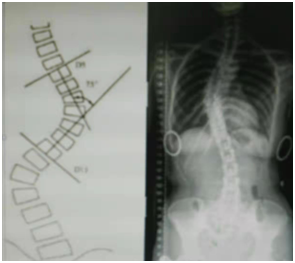

过去对脊柱侧弯患者一般要等到14岁左右再做脊柱矫正手术,儿童在等待手术期间因在生长发育期,侧弯会发展很快,畸形也会加剧,这时如不及时治疗和控制侧弯的发展,即使等到适合做手术的年龄,也增加了手术矫正难度。现在随着科学技术的发展,高分子合成材料的广泛应用,人们将医学和工程学结合起来,利用现代康复工程中的矫形器技术来矫治中轻度脊柱侧弯,矫正或控制畸形的发展。 脊柱侧弯的弯曲通常是用科学的Cobb法来评定。当Cobb角小于15- 20度时可在康复医生的辅导下坚持康复训练,一般得到控制和恢复,但必须定期复查。当Cobb角大于20度,小于45-50度时必须穿戴矫形器进行矫治,防止侧弯加剧。当Cobb角大于50度时就应考虑施行脊柱矫形手术进行矫正。

脊柱侧弯矫形器,就是利用三点作用力的原理,使儿童在生长过程中得到矫正。由于每个人侧弯的部位、弯曲的程度及身体的轮廓都不一样,因此脊柱侧弯矫形器是根据患者X光片的侧弯情况并结合人体外形,因人而异取模订制的。其施力方向,部位必须满足人体生物力学及矫正要求。